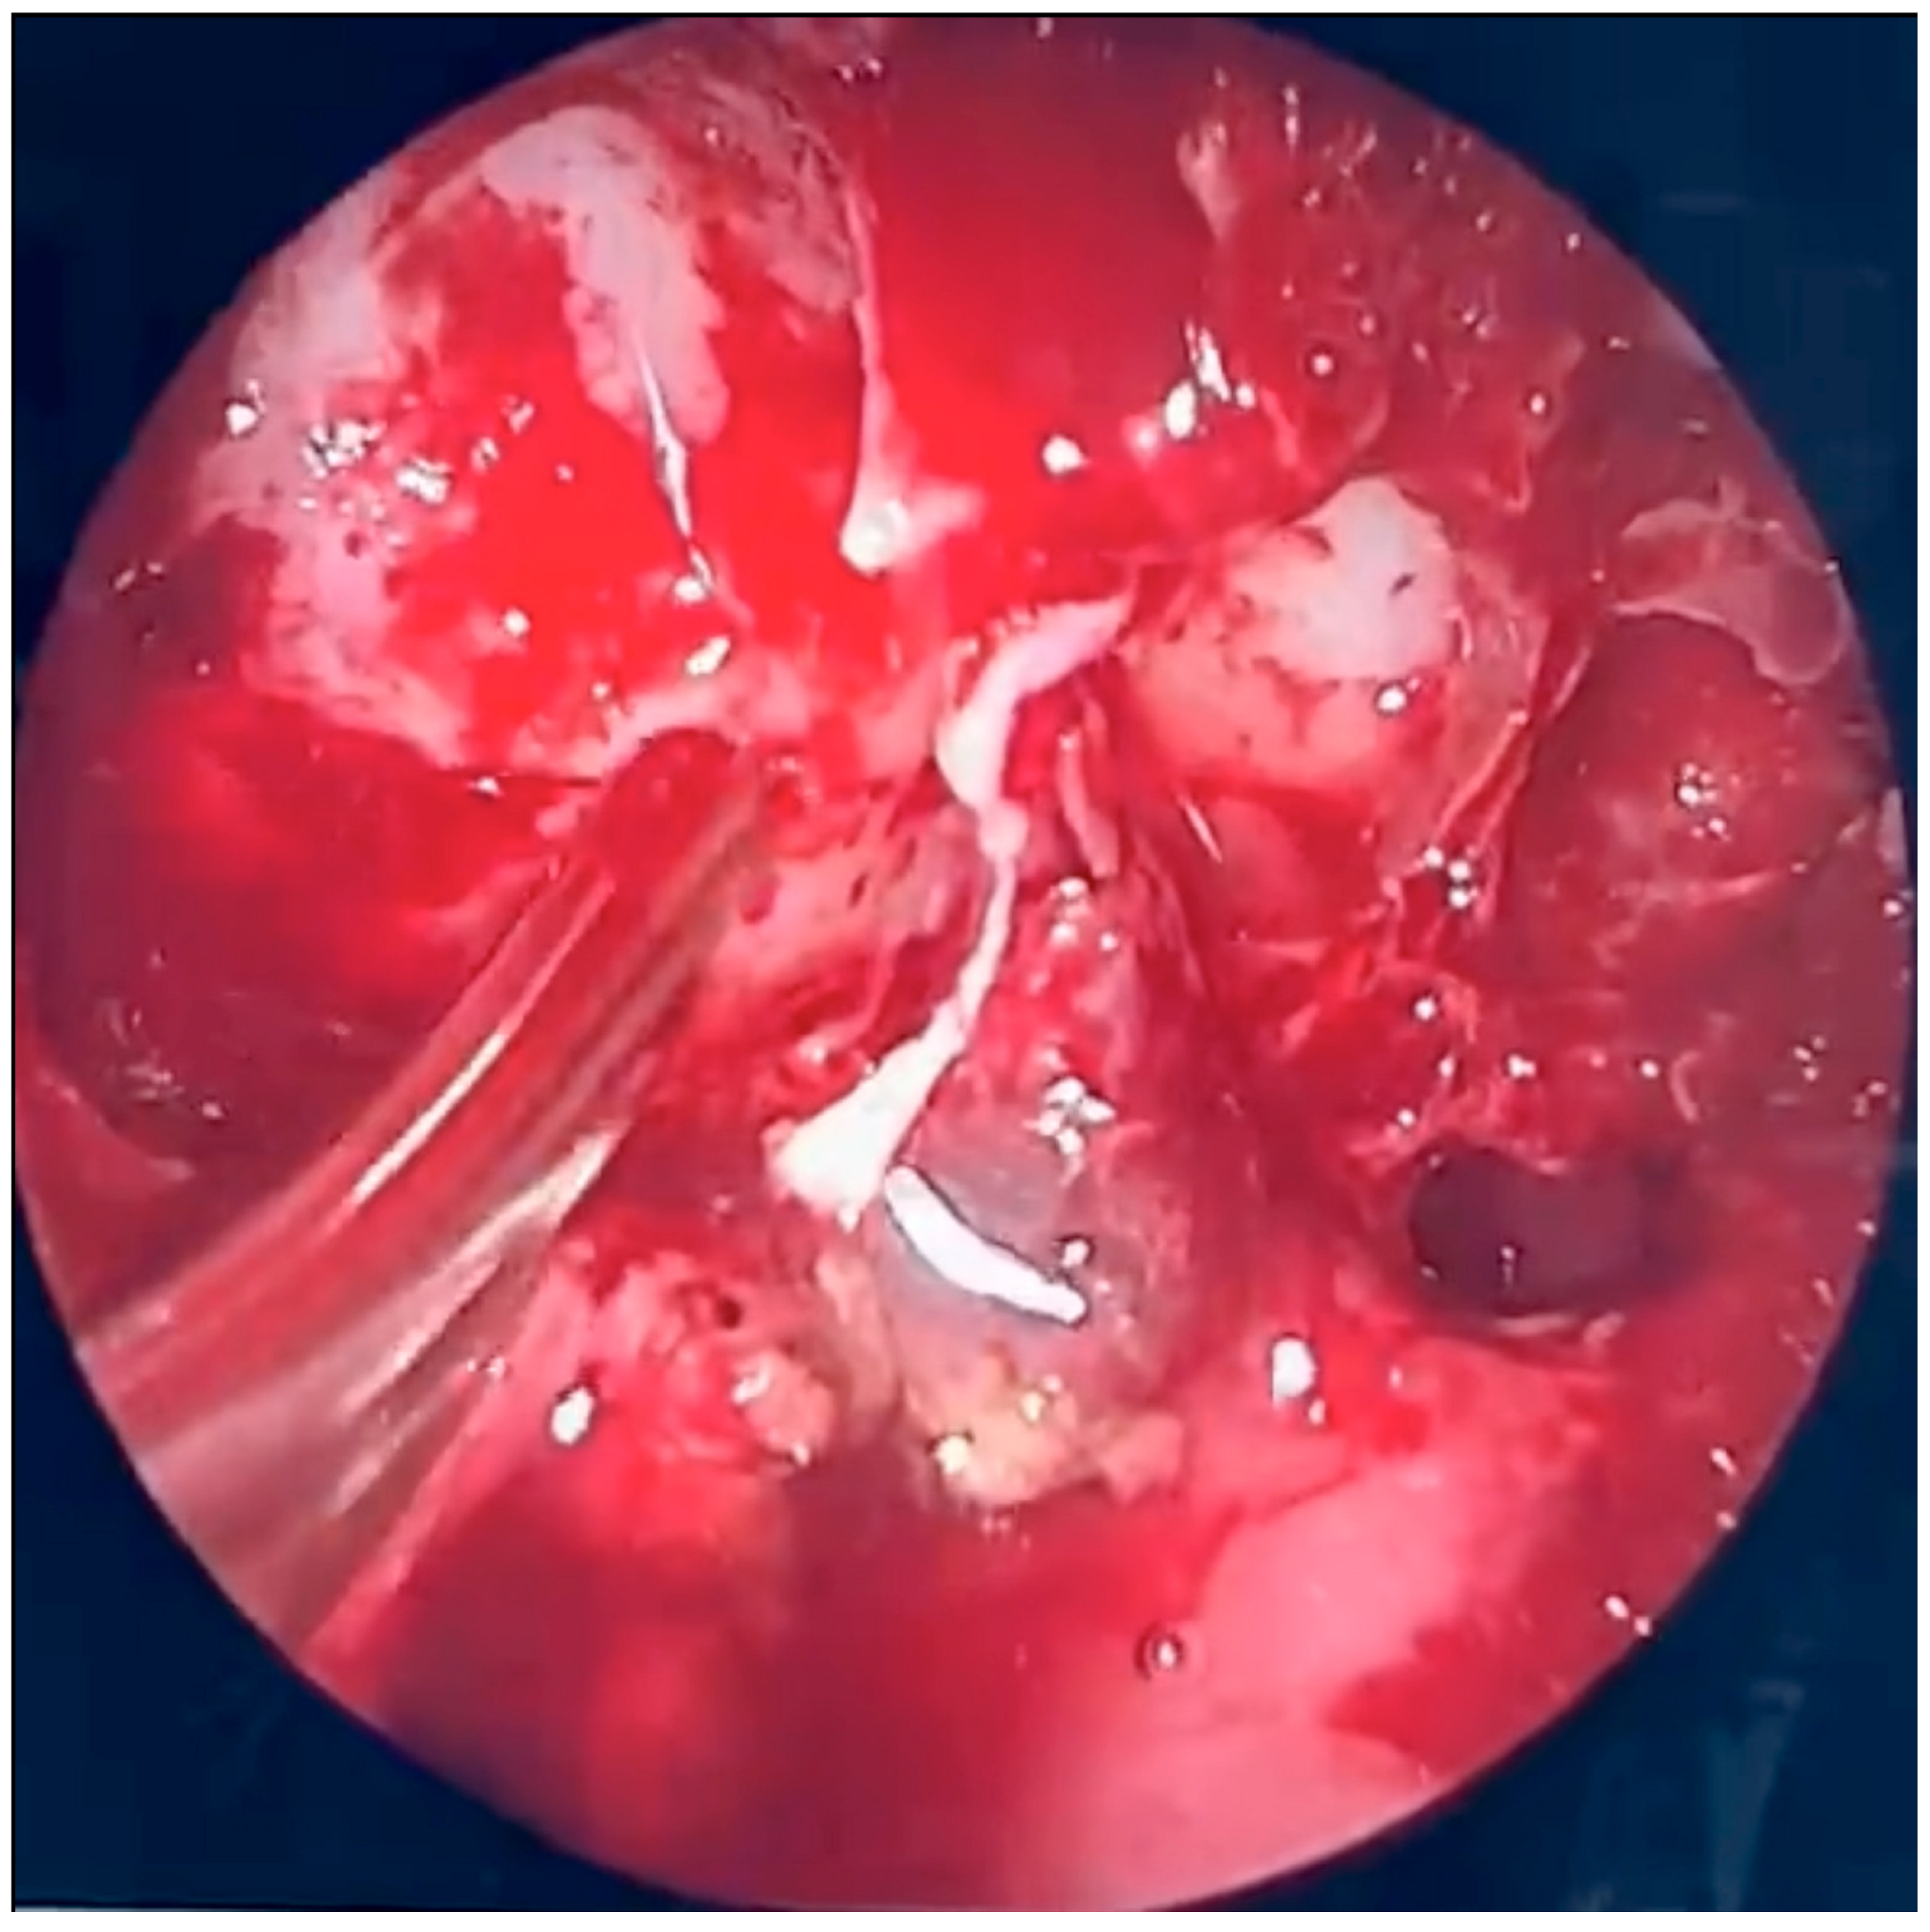

2.2. Operative Report: Urgent Endoscopic Sinus Surgery

The patient was scheduled for urgent endoscopic debridement due to suspected fungal sinonasal infection. Following decongestion (anemization) of the nasal mucosa on the right side, extensive inflammatory lesions consistent with fungal morphology were visualized. These changes had caused significant destruction of the middle nasal concha as well as the ethmoidal labyrinth. Endoscopic removal of the pathological tissue was performed, encompassing both the anterior and posterior ethmoid sinuses. The natural openings of the maxillary, sphenoid, and frontal sinuses were subsequently identified, surgically opened, and widened. Fungal lesions were thoroughly debrided from the maxillary sinus. Upon accessing the frontal sinus, purulent discharge was encountered and evacuated.

During further inspection, a bony defect of the lamina papyracea was identified in its anterior portion, measuring approximately 4 mm in diameter. The lamina papyracea was resected further, extending posteriorly to the level of the posterior ethmoid cells. A horizontal incision was then made in the orbital periosteum, which allowed for partial herniation of the orbital fat into the ethmoid cavity—facilitating access and drainage. Anterior nasal packing using Merocel was placed to support mucosal healing and maintain patency. Figure 3, Figure 4 and Figure 5 present the intraoperative view.

Figure 3. Endoscopic surgery: intraoperative view showing nasal cavity filled with fungal masses.